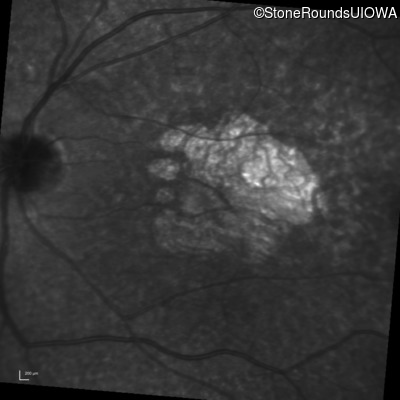

This 30 year old man first noticed poor vision in dim light when he was five years old. His visual acuity began to fall in his early 20's.

Diagnosis & molecular findings

Disease Gene Allele 1 variant(s) Allele 2 variant(s) Inheritance mode

Macular Disease WDR19 His344Arg CAT>CGT Ser485Ile AGT>ATT AR